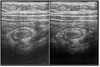

What are the ultrasound signs of Hypertrophic Pyloric Stenosis?

Doughnut” or “target” on transverse image (thick wall around pylorus)

What pathology is shown here?

Hypertrophic Pyloric Stenosis

Hypertrophic Pyloric Stenosis ## Footnote Lumen almost completely blocked off